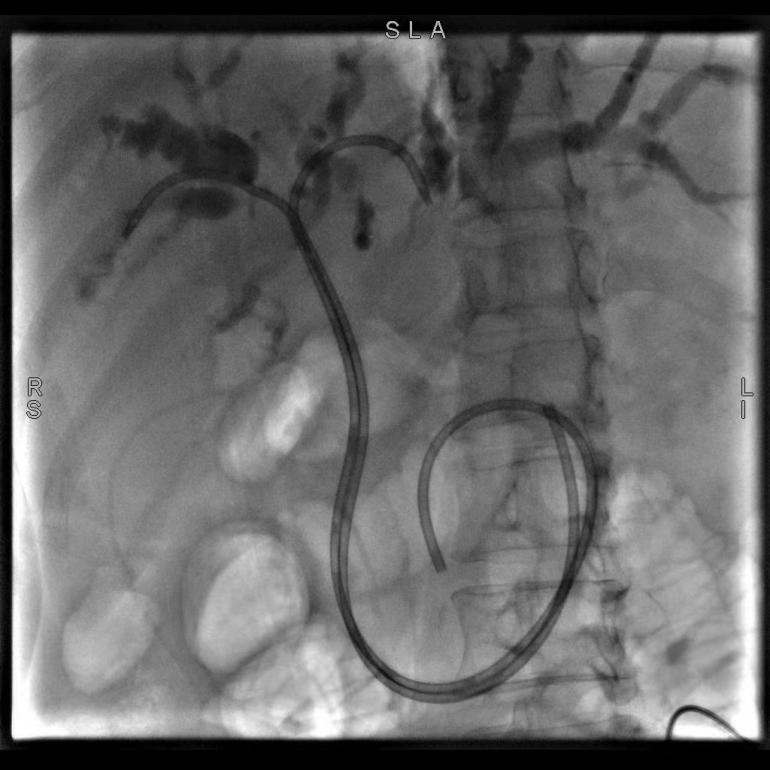

56岁的患者巫某,因“确诊结肠癌伴肝转移3年,皮肤巩膜黄染1周”入院,完善检查后,诊断为梗阻性黄疸、肝继发恶性肿瘤。陶锐主任医师组织团队在讨论了巫女士的病情后,决定实施ERCP+EST+ERBD术,术中主刀陶锐主任医师根据患者的病情置入了鼻胆管改良塑料支架,患者术后引流通畅,梗阻情况明显好转。

(图示为置入鼻胆管改良塑料支架)